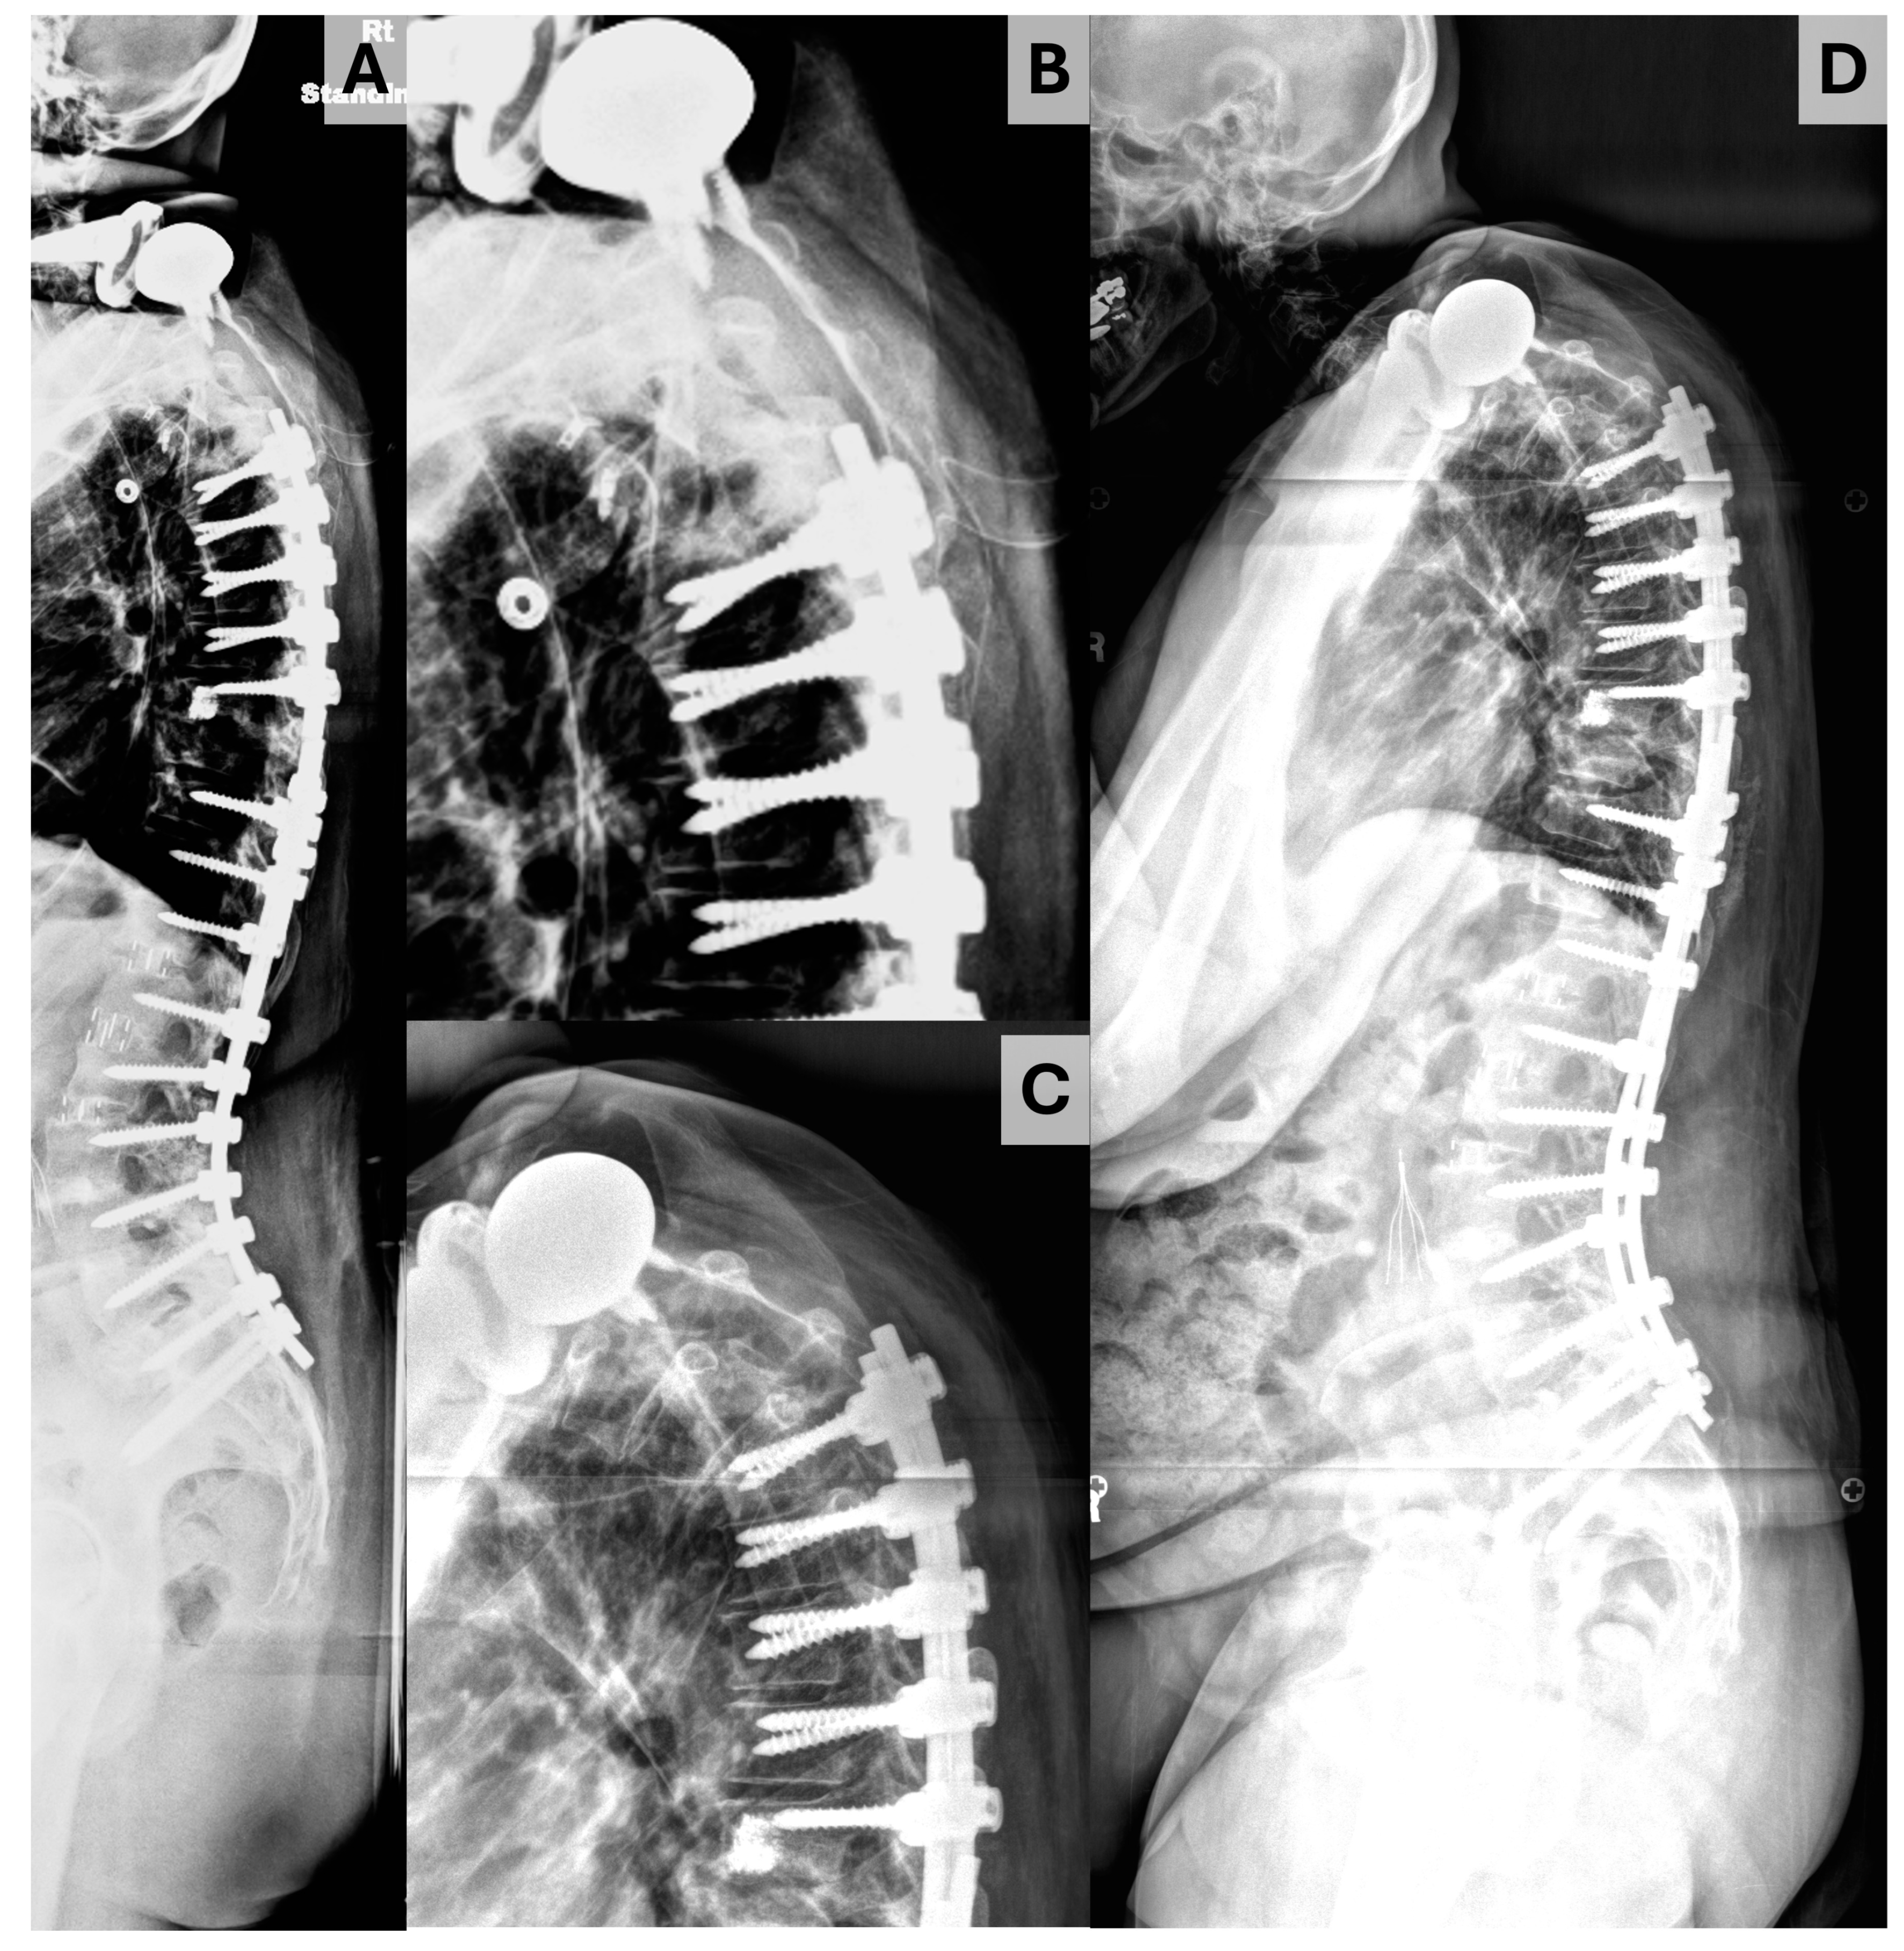

2. Materials and Methods